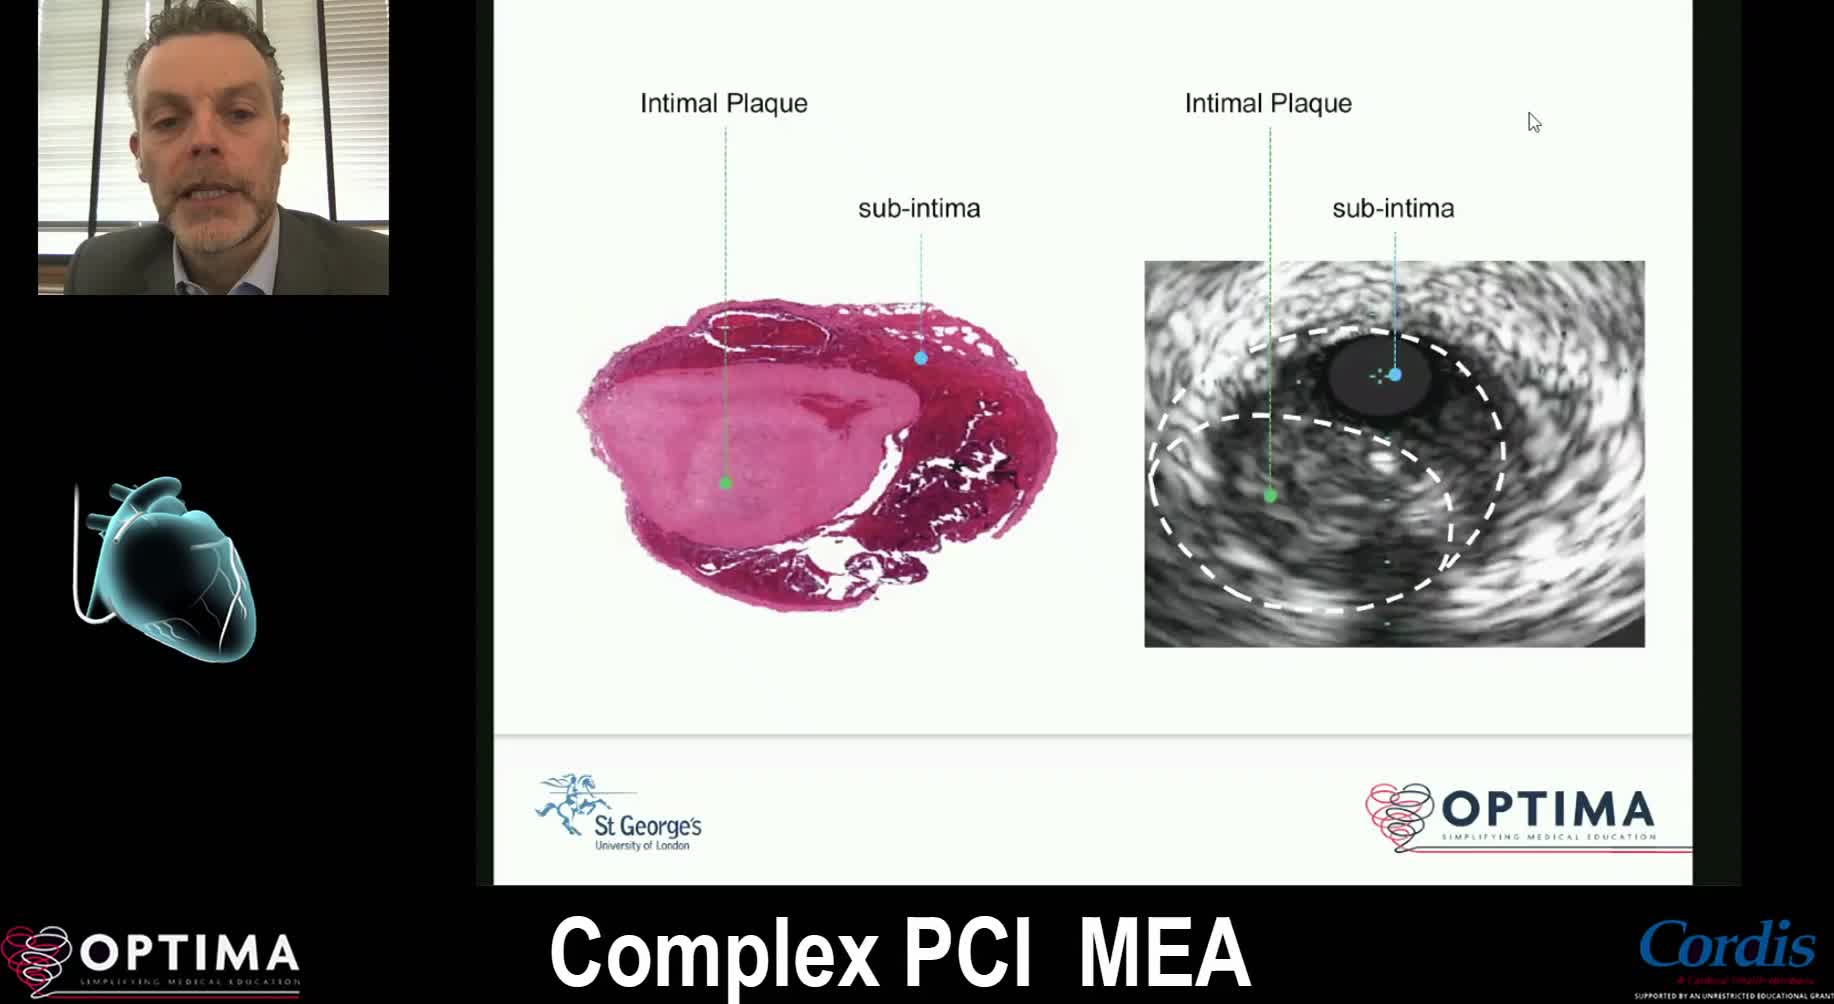

Complex PCI Middle East April 2021

Treatment of coronary arterial calcium (CAC) has being redefined. We explore the interaction between CAC and patient...